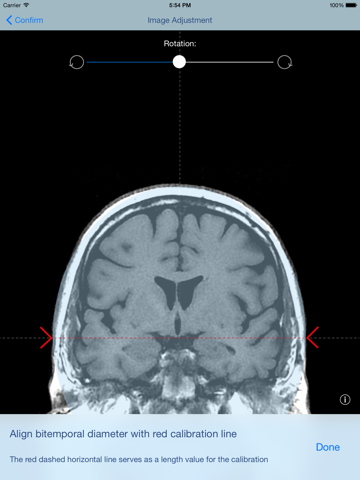

The Thomale Guide is a neurosurgical instrument and can be used as a navigation aid for the implantation of ventricular catheters via a frontal pre-coronary borehole for the treatment of hydrocephalus. With the aid of a coronal CT or MRT Scan this App can calculate the best entrance angle, the ventricular catheter length and the distance between borehole and median line.